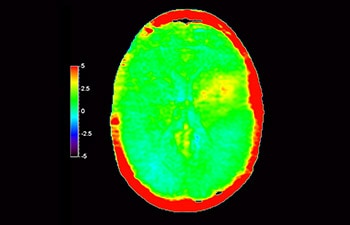

En una sociedad con una alta incidencia de trastornos neurológicos, Philips se compromete a ofrecer una excelente asistencia en el tratamiento y claridad en el diagnóstico para todos los pacientes. Hoy en día, aunque la RM es la modalidad de referencia para la adquisición de imágenes de neurooncología, su precisión a la hora de clasificar los tumores y de evaluar el seguimiento de los tratamientos aún tiene mucho margen de mejora. 3D APT (Amide Proton Transfer, transferencia de protones de amidas) es un exclusivo método de adquisición de imágenes por RM cerebral sin contraste que tiene por objetivo ofrecer un diagnóstico de neurooncología más fiable. 3D APT utiliza la presencia de proteínas celulares endógenas para producir una señal de RM que se corresponde directamente con la proliferación celular, que es un marcador de la actividad tumoral. 3D APT puede ayudar a los profesionales de la salud debidamente instruidos a diferenciar los gliomas de baja malignidad de los gliomas más graves, así como a diferenciar la progresión tumoral del efecto del tratamiento1.